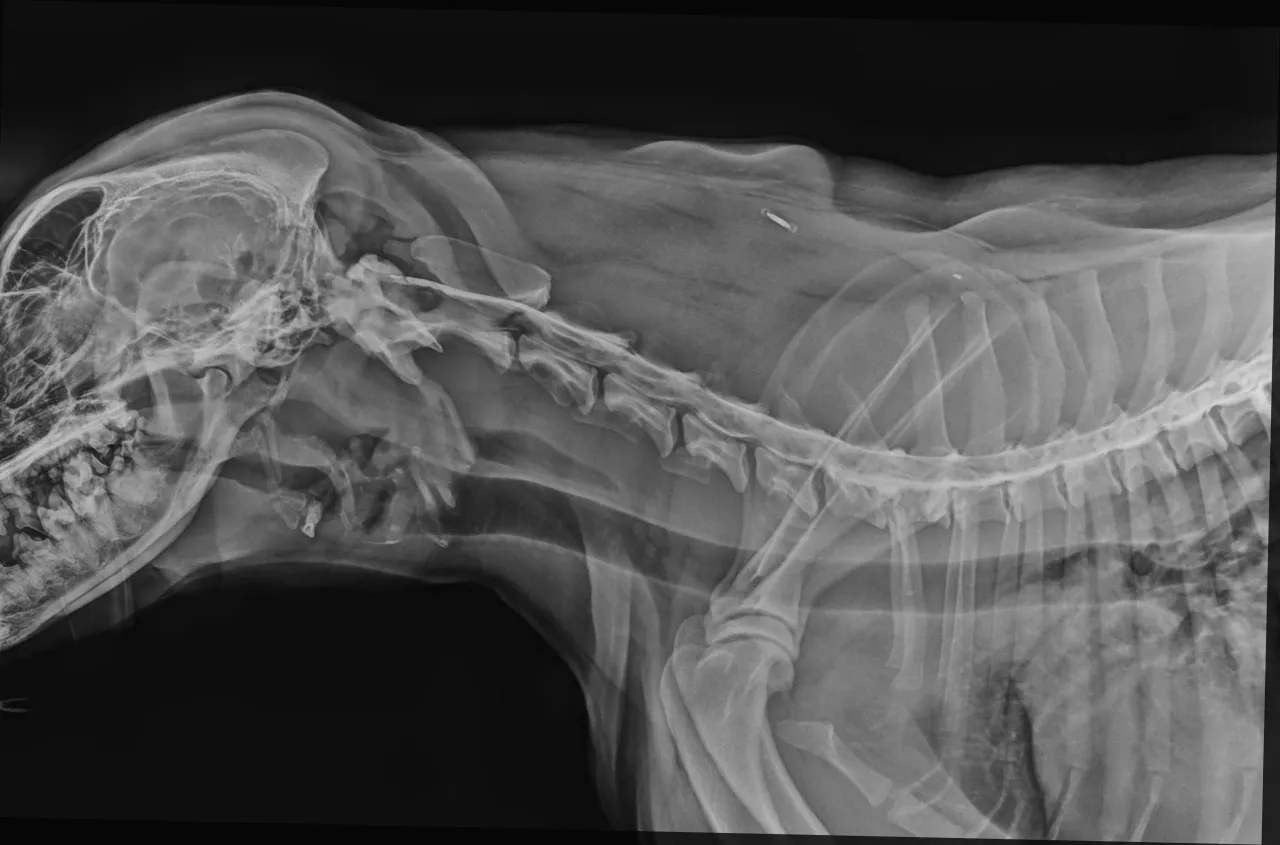

Pierwszym i podstawowym krokiem w gabinecie weterynarza jest dokładne badanie neurologiczne. To ono pozwala ocenić stopień uszkodzenia i zlokalizować problematyczny obszar. Muszę jednak podkreślić, że klasyczne zdjęcia rentgenowskie (RTG), choć pomocne w wykluczeniu innych schorzeń kostnych, są niewystarczające do jednoznacznego potwierdzenia dyskopatii i precyzyjnego zlokalizowania ucisku na rdzeń kręgowy. Rdzeń kręgowy i krążki międzykręgowe nie są widoczne na standardowym RTG.

Dlatego też, aby postawić trafną diagnozę i podjąć decyzję o dalszym leczeniu, niezbędne są bardziej zaawansowane metody obrazowania. Mówimy tu o tomografii komputerowej (TK) lub rezonansie magnetycznym (MRI). To właśnie te badania pozwalają nam, weterynarzom, zobaczyć struktury miękkie, takie jak rdzeń kręgowy i krążki, z niesamowitą precyzją. Dzięki nim możemy dokładnie zlokalizować miejsce ucisku, ocenić jego rozmiar i stopień, co jest kluczowe dla zaplanowania skutecznego leczenia.